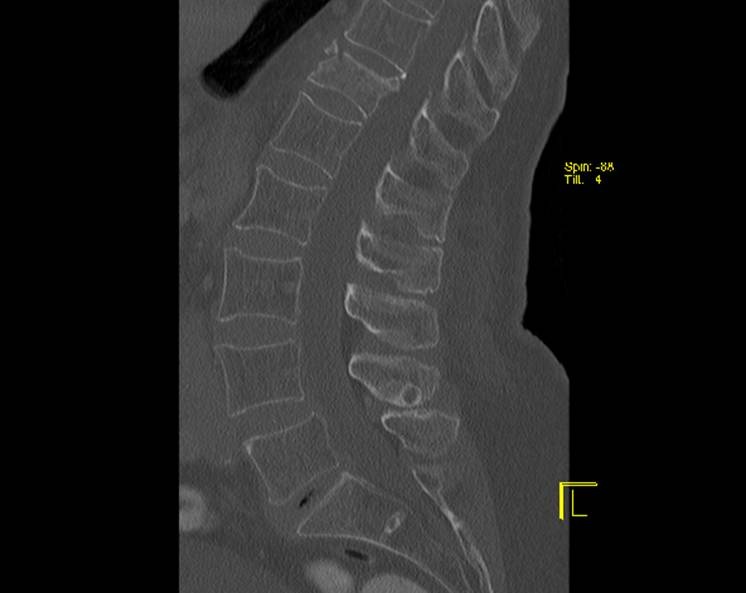

> Пациентка, 1934 г.р., постует 8 апреля к травматологам... упала дома на

> спину... сильные боли в области перехода грудного в поясничный отдел

> позвоночника... Рентген... (первые две картинки)

> там вроде компрессионный перелом, но толи свежий, толи старый... не совсем

> понятно...

> Выполняют КТ-позвоночника... (Третья и четвертая картинки)

Какая-то округлая тень над левой почкой, причем не только по СТ это видно.

Может это и есть основной причиной болей?